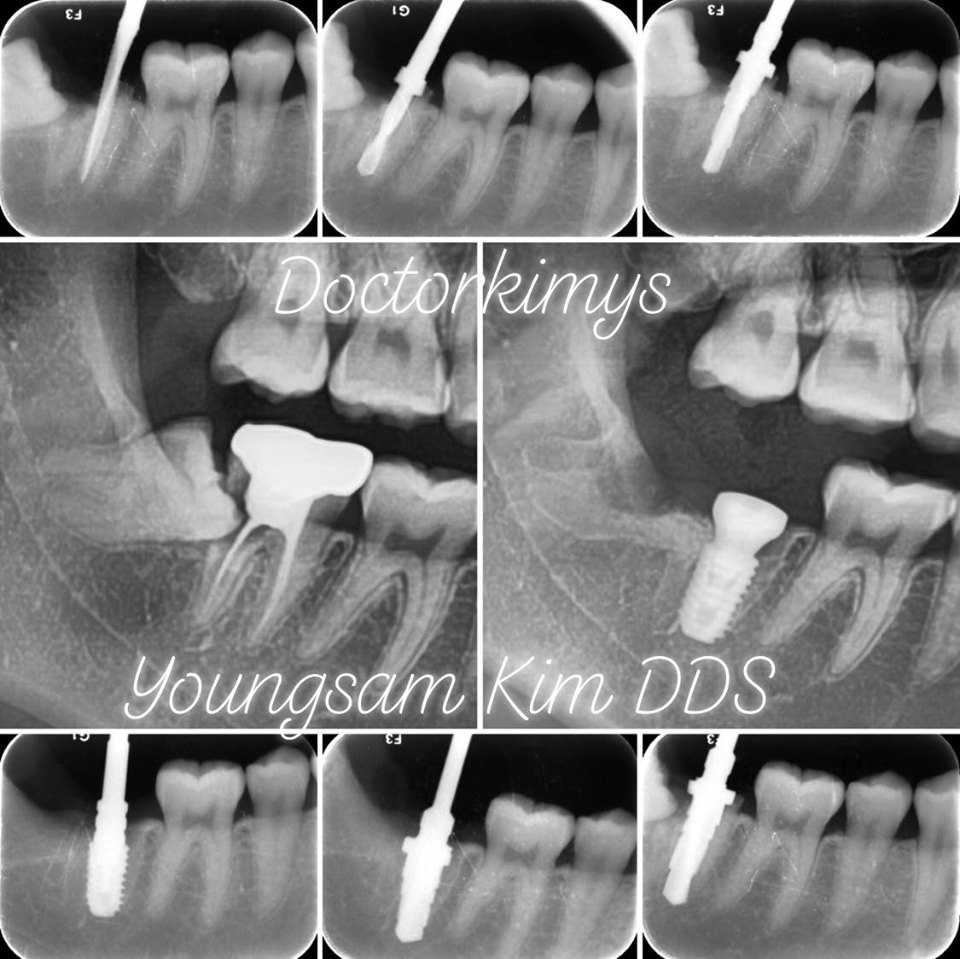

많은 사람들이 이렇게 알고 있는데 사실 발치 즉시 식립이라고 불리는 수술이죠. 얼마 전에 사랑니를 뽑으러 오셨다가 그 앞에 있는 큰어금니까지 뽑은 케이스가 있었어요. 누워서 난 사랑니가 앞 어금니의 중간과 뿌리 부분에 충치를 발생!! 이 대구치는 기존에 신경치료를 받은 경험이 있어 통증을 느끼질 못했던 거죠. 우식증이 커질대로 커지고 심지어 뿌리쪽까지 진행이 되어서 도저히 살리기 힘든 경우였지요. 참 안타깝죠. 신경치료를 한 이는 문제가 생겨도 아프지 않아서 이렇게까지 방치 되기 정말 쉬워요. 그래서 꼭 3~6개월에 1번씩 정기검진을 가는 게 중요하죠. 틈틈히 체크를 해서 충치를 초기에 발견했다면 사랑니 뽑고 다시 치료할 수 있었을텐데.. 결국 사랑니와 함께 제2대구치 발거 판정을 받을 수밖에 없었죠. 그치만, 이렇게 뽑은 날 원데이로 임플란트 수술까지 하기로 하였습니다. 심을 때 원래 치근의 방향, 각도대로 심어주는 것이 핵심이죠. 그래야 추후에 인공보철물이 올라갈 때 기존의 자연치처럼 좋은 위치로 셋팅될 수 있죠. 저희 원장님께선 공간감각이 워낙 좋아서 여러 개를 심어도 픽스처 각도가 완벽! 다음엔 여러 개를 한꺼번에 심은 사례를 준비해 소개할께요.

강남레옹치과에선 요즘 이런 사례에선 종종 발치 즉시 식립을 해요. 임상경력이 워낙 많아 이럴 땐 잇몸이 아물은 후에 심는 것과 큰 차이가 없다는 생각이시죠. 전에는 잘 안하셨는데 1차 안정성도 그렇고 깊이가 잘 조절되는 한 요즘은 원데이를 더 선호해요. 저희 의료진은 자연치아를 누구보다 아껴서 왠만하면 살려주는데도 딱 봤을 때 이건 아니다 싶을 때만 이런 결정을 내리신거죠. 얼마 못가 치아 머리가 똑 하고 파절되어 탈락이 될 가능성이 정말 크기 때문이에요.

또 한 케이스. 이분은 이미 치관이 부러졌습네요. 남은 뿌리를 제거하고 그 자리에 고정체를 심었죠. 그 주변으로는 조직이 잘 아물도록 도움을 주는 치유지혈보조제를 넣습니다. 보통 사랑니를 뽑을 때 쓰는데 이렇게 절개를 하지 않고 바로 심은 경우에도 사용을 하죠. 치유에 정말 도움이 많이 된다 생각이 드네요.